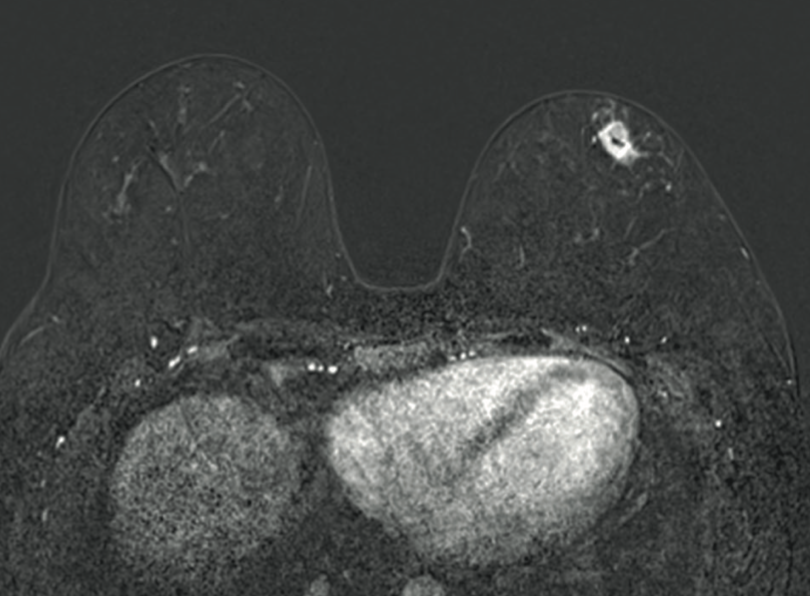

Material y Métodos: Se presentan 19 pacientes con CMTN diagnosticado entre Junio/2022 y Junio/2024 que recibieron terapia neoadyuvante con pembrolizumab y quimioterapia según el protocolo Keynote-522 y posteriormente cirugía según indicación.

Resultados: De las 19 pacientes, 1 se etapificó como IA, 8 estadio IIA, 8 estadio IIB, 1 estadio IIIA y 1 estadio IIIB. Todas fueron sometidas a tratamiento quirúrgico, 15 de ellas presentando respuesta patológica completa y 4 respuesta patológica parcial. En el seguimiento, 16 de ellas tuvo una respuesta imagenológica completa. 1 paciente suspendió tratamiento por efectos adversos mayores.